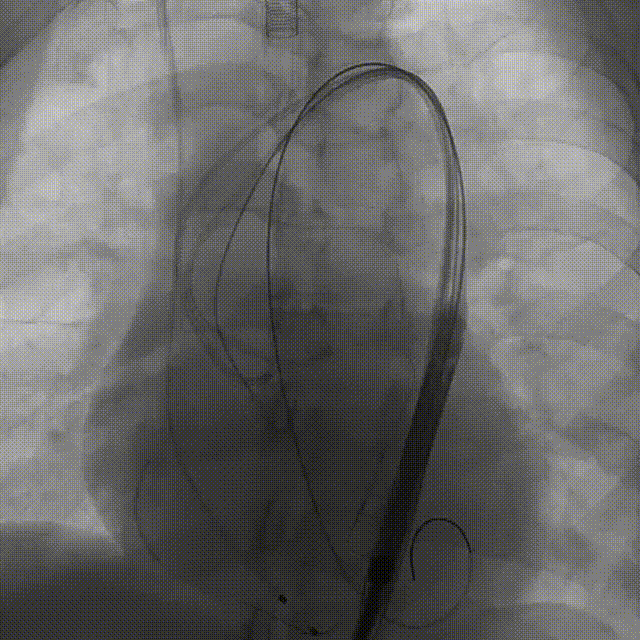

手术过程概览

1.主动脉根部造影

2.18mm球囊预扩

3.左冠造影

4.左冠行支架保护

5.右冠行支架保护

6.右冠造影

7.输送器过弓

8.瓣膜定位

9. 工作位评估冠脉

10.右冠行烟囱支架技术

11.左冠造影评估灌注正常,

撤出支架

12.术后造影